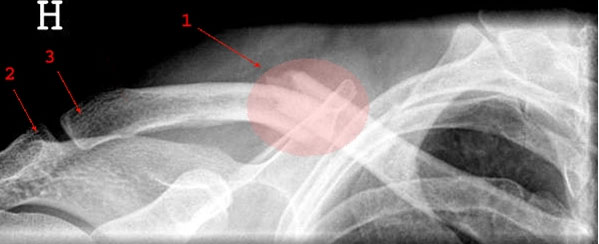

Lægen stiller normalt diagnosen ud fra røntgenbillede(r).

Supplerende CT-skanning eller MR-skanning kan evt. være nødvendig, hvis der er brug for at se flere detaljer ved knoglebruddet.

For at være helt sikker på, at der er et brud, og for at sikre god behandling, vil der altid blive taget røntgenbilleder af den skadede kropsdel eller område.